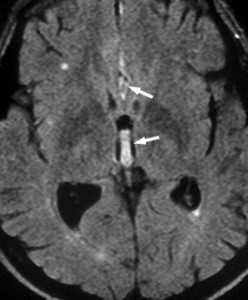

МРТ головного мозга. Аксиальная Т2-зависимая МРТ и сагиттальная Т1-зависимая МРТ с контрастированием. Медуллобластома (стрелки) с компрессией IV желудочка.

При МРТ головного мозга обычно выявляется однородное образование по средней линии в нижних отделах мозжечка, гипоинтенсивное на Т1-зависимых МРТ. На Т2-зависимых МРТ она, как правило, гиперинтенсивна, хотя встречаются исключения. Внутренняя структура опухоли обычно однородная, Кальцификаты, зоны некроза и кисты наблюдаются в 10-15% случаев. Контрастирование при МРТ хорошее, однородное. Гидроцефалия имеется почти у всех больных. Часто встречаются лептоменингеальные метастазы, определяемые при МРТ позвоночника.

У детей в мозжечке располагаются медуллобластомы, которые относятся к эмбриональным очень злокачественным опухолям. Она быстро растет по средней линии вдоль червя мозжечка обтурируя IV желудочек и вызывая окклюзионную гидроцефалию. Спускаясь вниз, опухоль может проходить через большое затылочное отверстие в большую цистерну. Медуллобластома метастазирует по ликворным путям и в 5% случаев гематогенно в лимфоузлы, кости и печень.